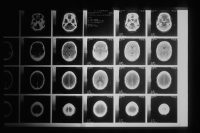

Ένας ανώτερος Καναδός ομοσπονδιακός επιστήμονας υποστηρίζει ότι η κυβέρνηση απέκλεισε την έρευνα για μια μυστηριώδη εγκεφαλική ασθένεια στο Νιου Μπράνζουικ, η οποία, όπως πιστεύει, μπορεί να έχει επηρεάσει 350 άτομα.

Οι αξιωματούχοι Υγείας στην ανατολική επαρχία δήλωσαν για πρώτη φορά το 2021 ότι 40 άτομα έπασχαν από μια ανεξήγητη νευρολογική πάθηση. Έναν χρόνο αργότερα μια επιτροπή που συγκάλεσε η επαρχία διαπίστωσε ότι οι ασθενείς πιθανώς είχαν υποβληθεί σε λανθασμένη διάγνωση και έπασχαν από άλλες ασθένειες.